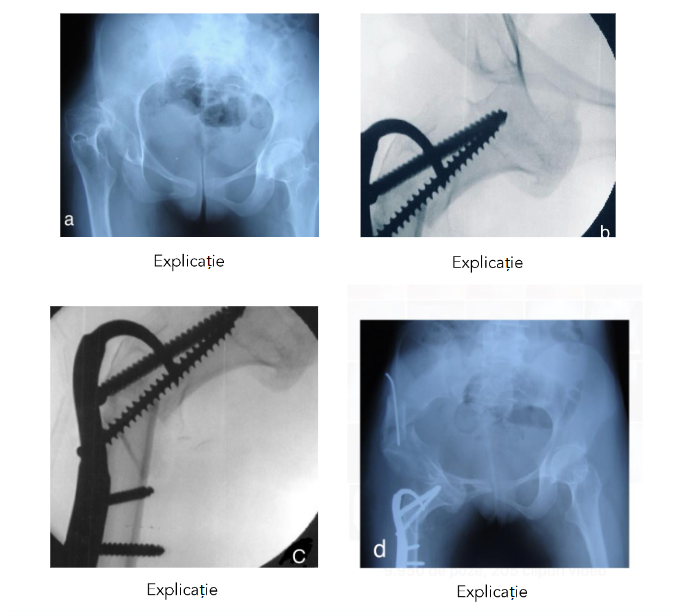

Fig. 3 Cephalo-obturatory neoacetabuloplasty in a 9.8-year-old female patient with a severe form of spastic paraparesis and unbearable pain at the level of the right hip:

a) dislocation of the right hip, coxa valga and antalgic position of the femur in adduction and internal rotation;

b) intraoperative verification of the position of the femoral head under the obturator ring;

c) fluoroscopic appearance of subtrochanteric osteotomy and trochantero-capital osteosynthesis;

d) radiological image 6 months postoperatively; the pain disappeared 30 days postoperatively and after 3 months she resumed walking.